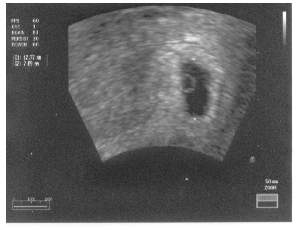

To moja niunia z 16 czerwca.